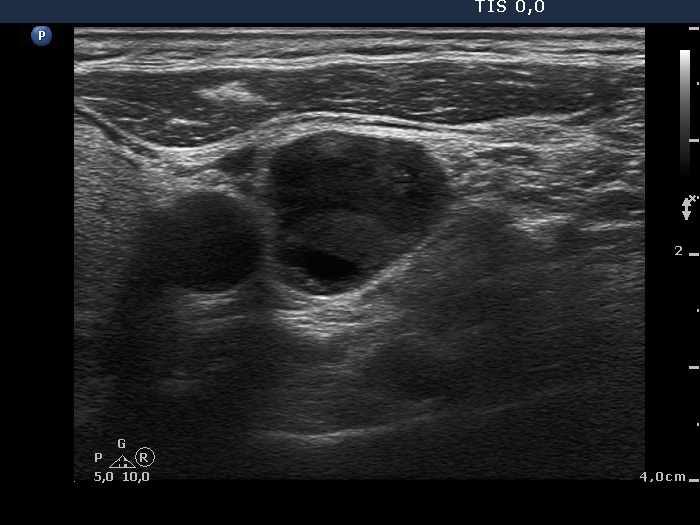

Intranodular hyperechogenic figures - case 779 (ultrasonographic picture 15)

Left side of the neck, another transverse scan. There is another metastatic lymph node.